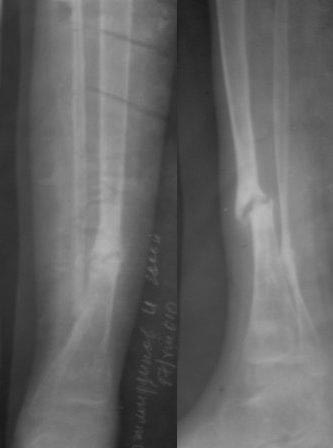

Сегодня сделал рентген, гвоздь сломался, видимо, усталостный перелом. Гвоздь и сломанная часть легко удалены, пока дистракционный остеосинтез аппаратом Илизарова, и будем постепенно исправлять деформацию. микрохирургия не доступна, оказалось, родители и повторный БИОС не могут из-за финансов,у читывая что ложный сустав не атрофичный и даже несколько гипертрофичный может продолжать аппаратное лечение? Или еще какие варианты? ,будем думать.